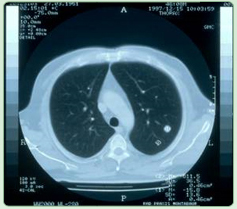

Lungenmetastasen vor OP

Lungenmetastase eines Dickdarm - CA's ( ED 11/97 ). Präoperative 2 malige Behandlung der Lungenmetastase mit Regionaler Tiefenhyerthermie |

Ergebnis: |

Die postoperative Aufarbeitung des Tumors ergab eine 70 % ige Nekrose (Zelltod) der |

Lungenmetastase; aus |

Mastall H. Zeit- und situatiosgerechte Einsatzmodelle für komplementäre Verfahren während |

konventionell-onkologischer Therapien. |

32. Medizinische Woche Baden-Baden 1998; 02.XI |